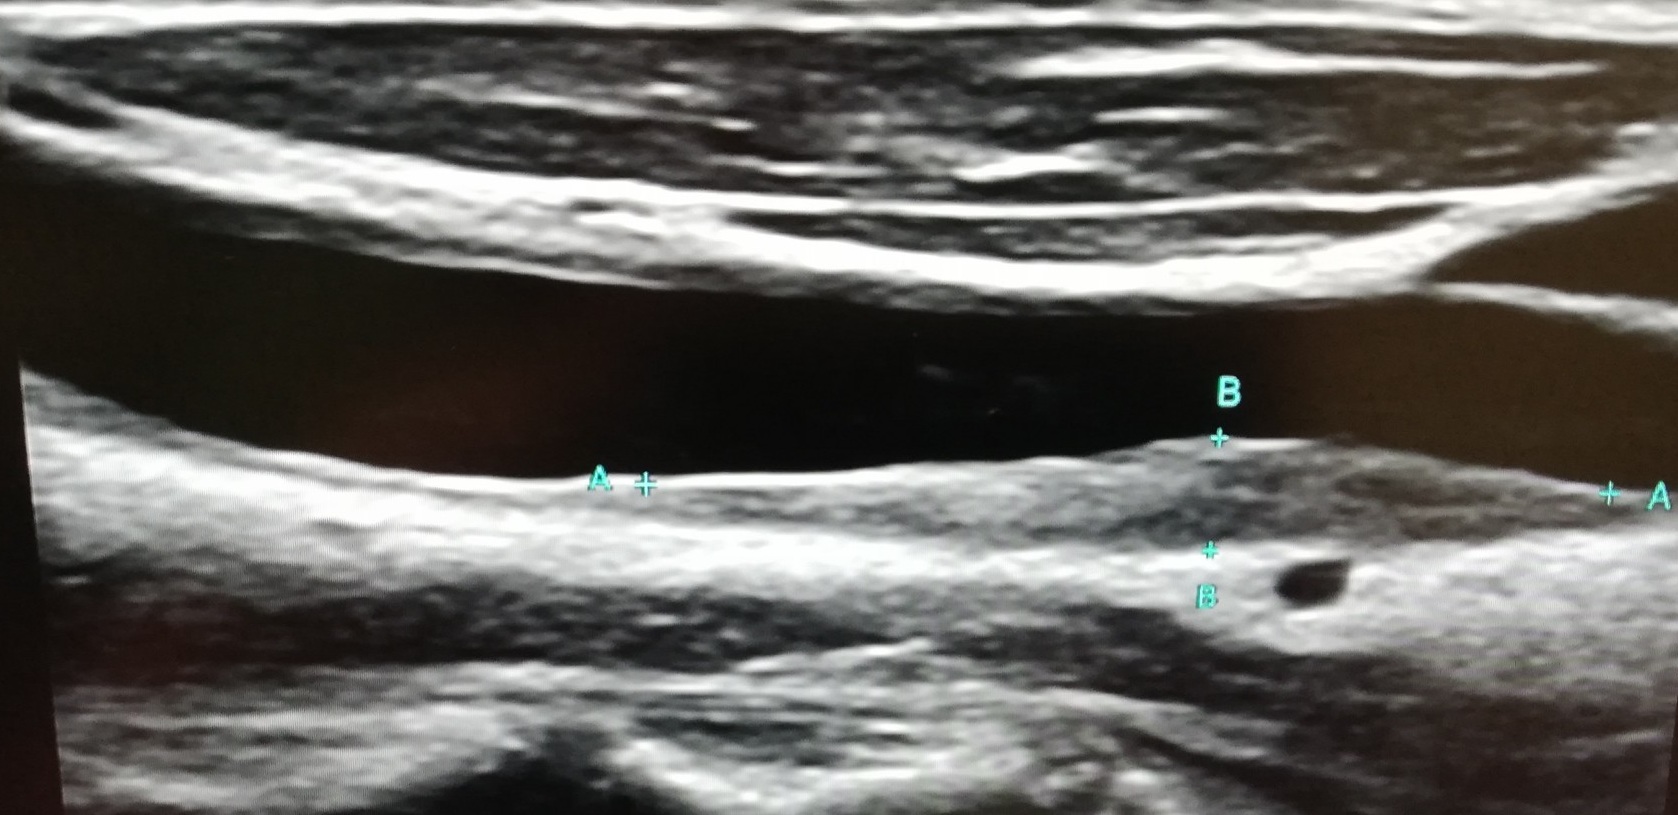

Sonografické vyšetření krčních tepen

Sonografické vyšetření krčních tepen slouží k detekci aterosklerotických změn v krčních tepnách. Přítomnost aterosklerotických změn poukazuje na zvýšené kardiovaskulární riziko a nutnost farmakologické intervence.